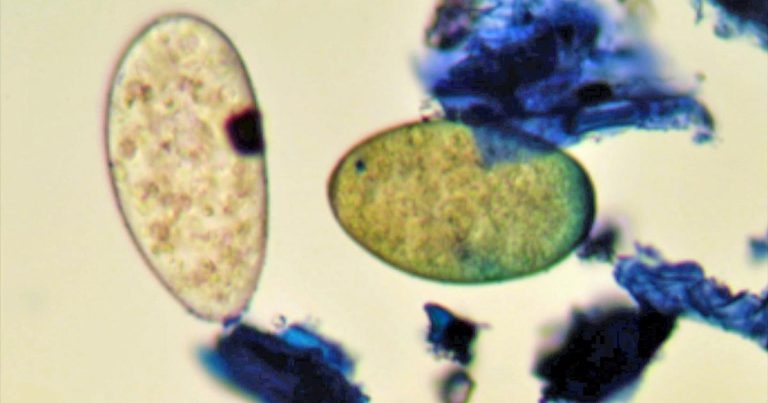

One advantage of the FEC test is it allows discrimination of liver fluke from rumen fluke eggs (Figure 2), with the former yellow and the latter colourless.